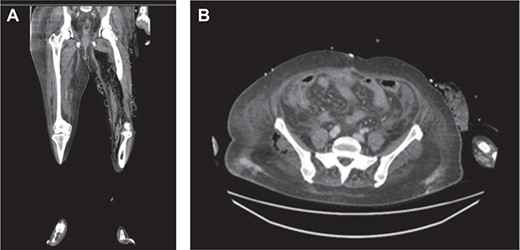

(a) Air in the deep medial and posterior compartments of the thighs and calf suggestive of residual infection in the deep compartment. (b) New finding of air in the right gluteus medius muscle.

Within 14 hours postoperatively, she developed an erythematous patch on her left thigh, and a creatine kinase of 19 000. A bedside finger test was performed which showed dirty dishwater fluid, necrotic fat and lack of bleeding. She was taken to theatre for urgent debridement for suspected NF. Antibiotics were changed to Meropenem, Vancomycin, Lincomycin and Fluconazole. She had extensive debridement of the soft tissue circumferentially on the left thigh, including some muscle. In 10 hours postdebridement, there was a radiological evidence of disease progression with gas in muscle compartments on the lower limb X-rays (Fig. 2a and b), and CT abdomen and lower limbs demonstrating gas throughout the whole left leg and a non-contiguous area in the right gluteal region (Fig. 3a and b). A diagnosis of multi-focal non-contiguous necrotising myositis was made.